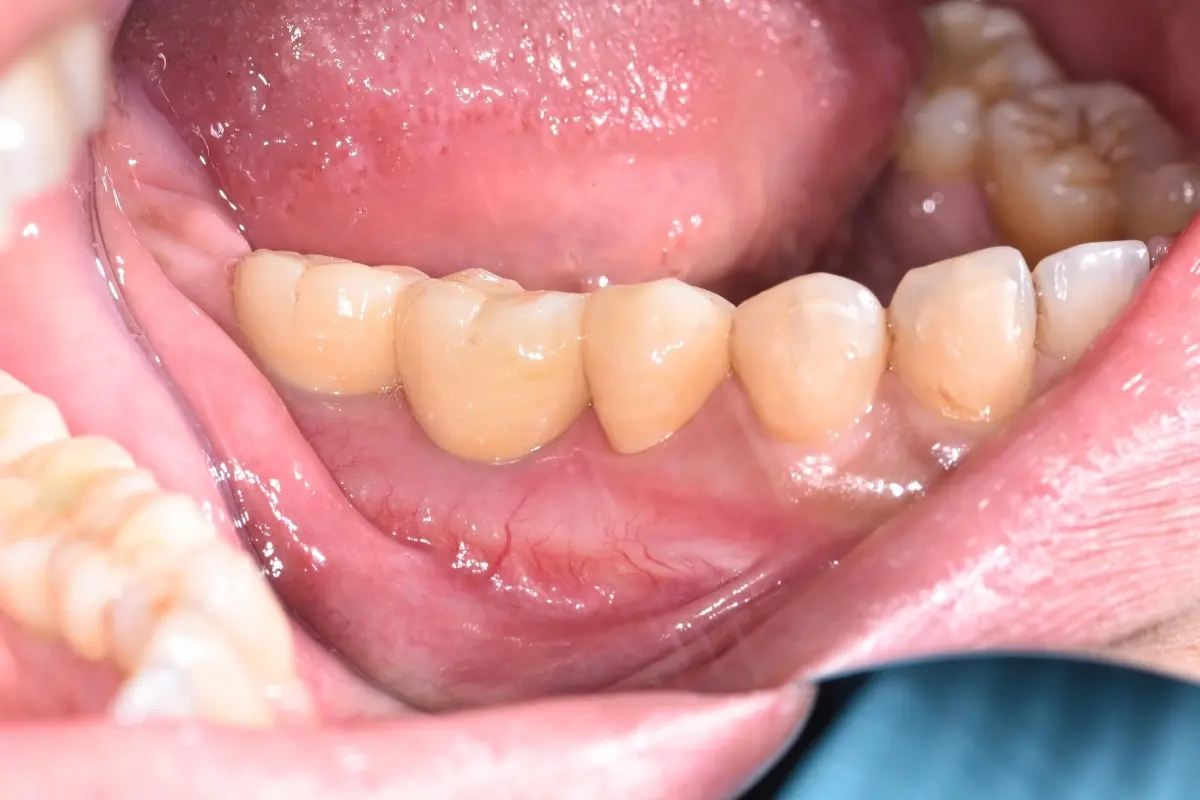

• 術前 43

術後 41

牙橋

主治醫師

• 楊明憲

治療時間

約1年4個月

主訴

吃東西左邊後牙會痛